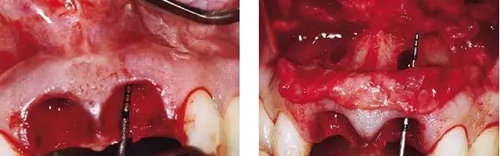

圖2、翻開(kāi)全厚瓣可見(jiàn)明顯的牙根縱裂,唇側(cè)骨板2/3受到累及而缺損。

圖3、拔牙后看到更大范圍的骨缺損,并且缺損導(dǎo)致上頜側(cè)切牙根尖牙骨質(zhì)暴露,繼而存在術(shù)后由于軟硬組織退縮而帶來(lái)的美學(xué)風(fēng)險(xiǎn)。

圖4、植入的種植體,初始穩(wěn)定性很好,由于骨缺損范圍大,選擇潛入式愈合。

圖5、種植體完全位于拔牙窩骨壁包圍的范圍內(nèi),距離唇側(cè)骨板至少2mm。